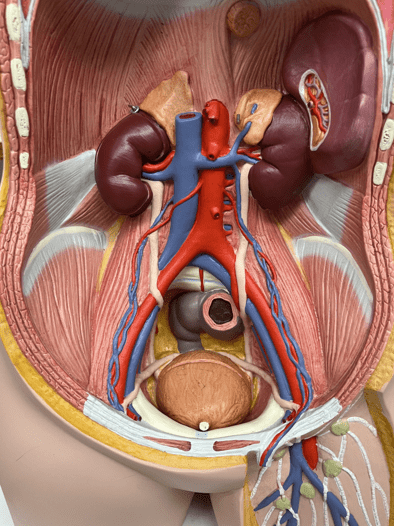

tunica externa

• Composed of loose connective tissue and collagen fibers.

7

New cards

external elastic membrane

• A thin layer of elastic connective tissue.

• Found between the tunica externa and tunica media.

• Found between the tunica externa and tunica media.

8

tunica media

• The middle layer of an artery wall.

• Composed of smooth muscle and elastic fibers.

• The smooth muscle allows for vasoconstriction and vasodilation.